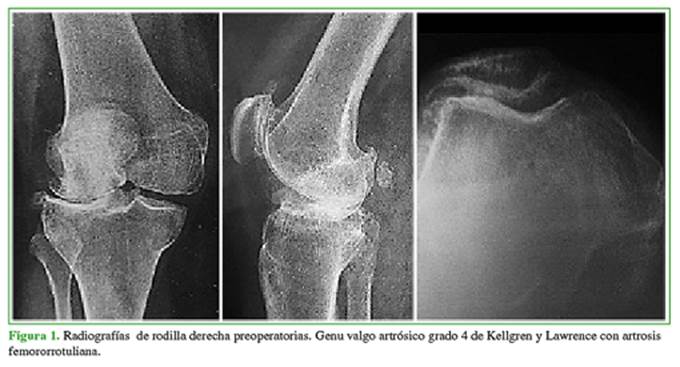

Antes de la cirugía, se tomaron radiografías de ambas rodillas, de frente y de perfil con carga bipodálica, axial de rótula a 30º de flexión (Merchant), de frente en semiflexión de 45º (Schuss), y radiografías en varo y valgo forzado para evaluar la suficiencia de los ligamentos colaterales, la corrección del deseje y el pinzamiento del compartimento contralateral (Figura 1). En el posoperatorio, se tomaron radiografías de rótula, de frente, de perfil y axial.

Evaluación radiográfica preoperatoria femorotibial: todos los casos correspondieron al estadio 4 en la clasificación de Kellgren y Lawrence en el compartimento externo; se observaron dos casos de subluxación en el plano coronal. El eje preoperatorio fue de 12,3º ± 4,1º de valgo, se destacaban 10 casos de valgo >15º, entre ellos, tres casos severos de 20º, reductibles en maniobras de varo-valgo forzado. Evaluación radiográfica posoperatoria femorotibial: el eje fue de 5,2º ± 3,1º de valgo (p <0,001) (Figura 3). Se detectó la progresión del proceso degenerativo artrósico en el compartimento medial en un paciente, que desarrolló cambios grado 2 y sintomatología interna.